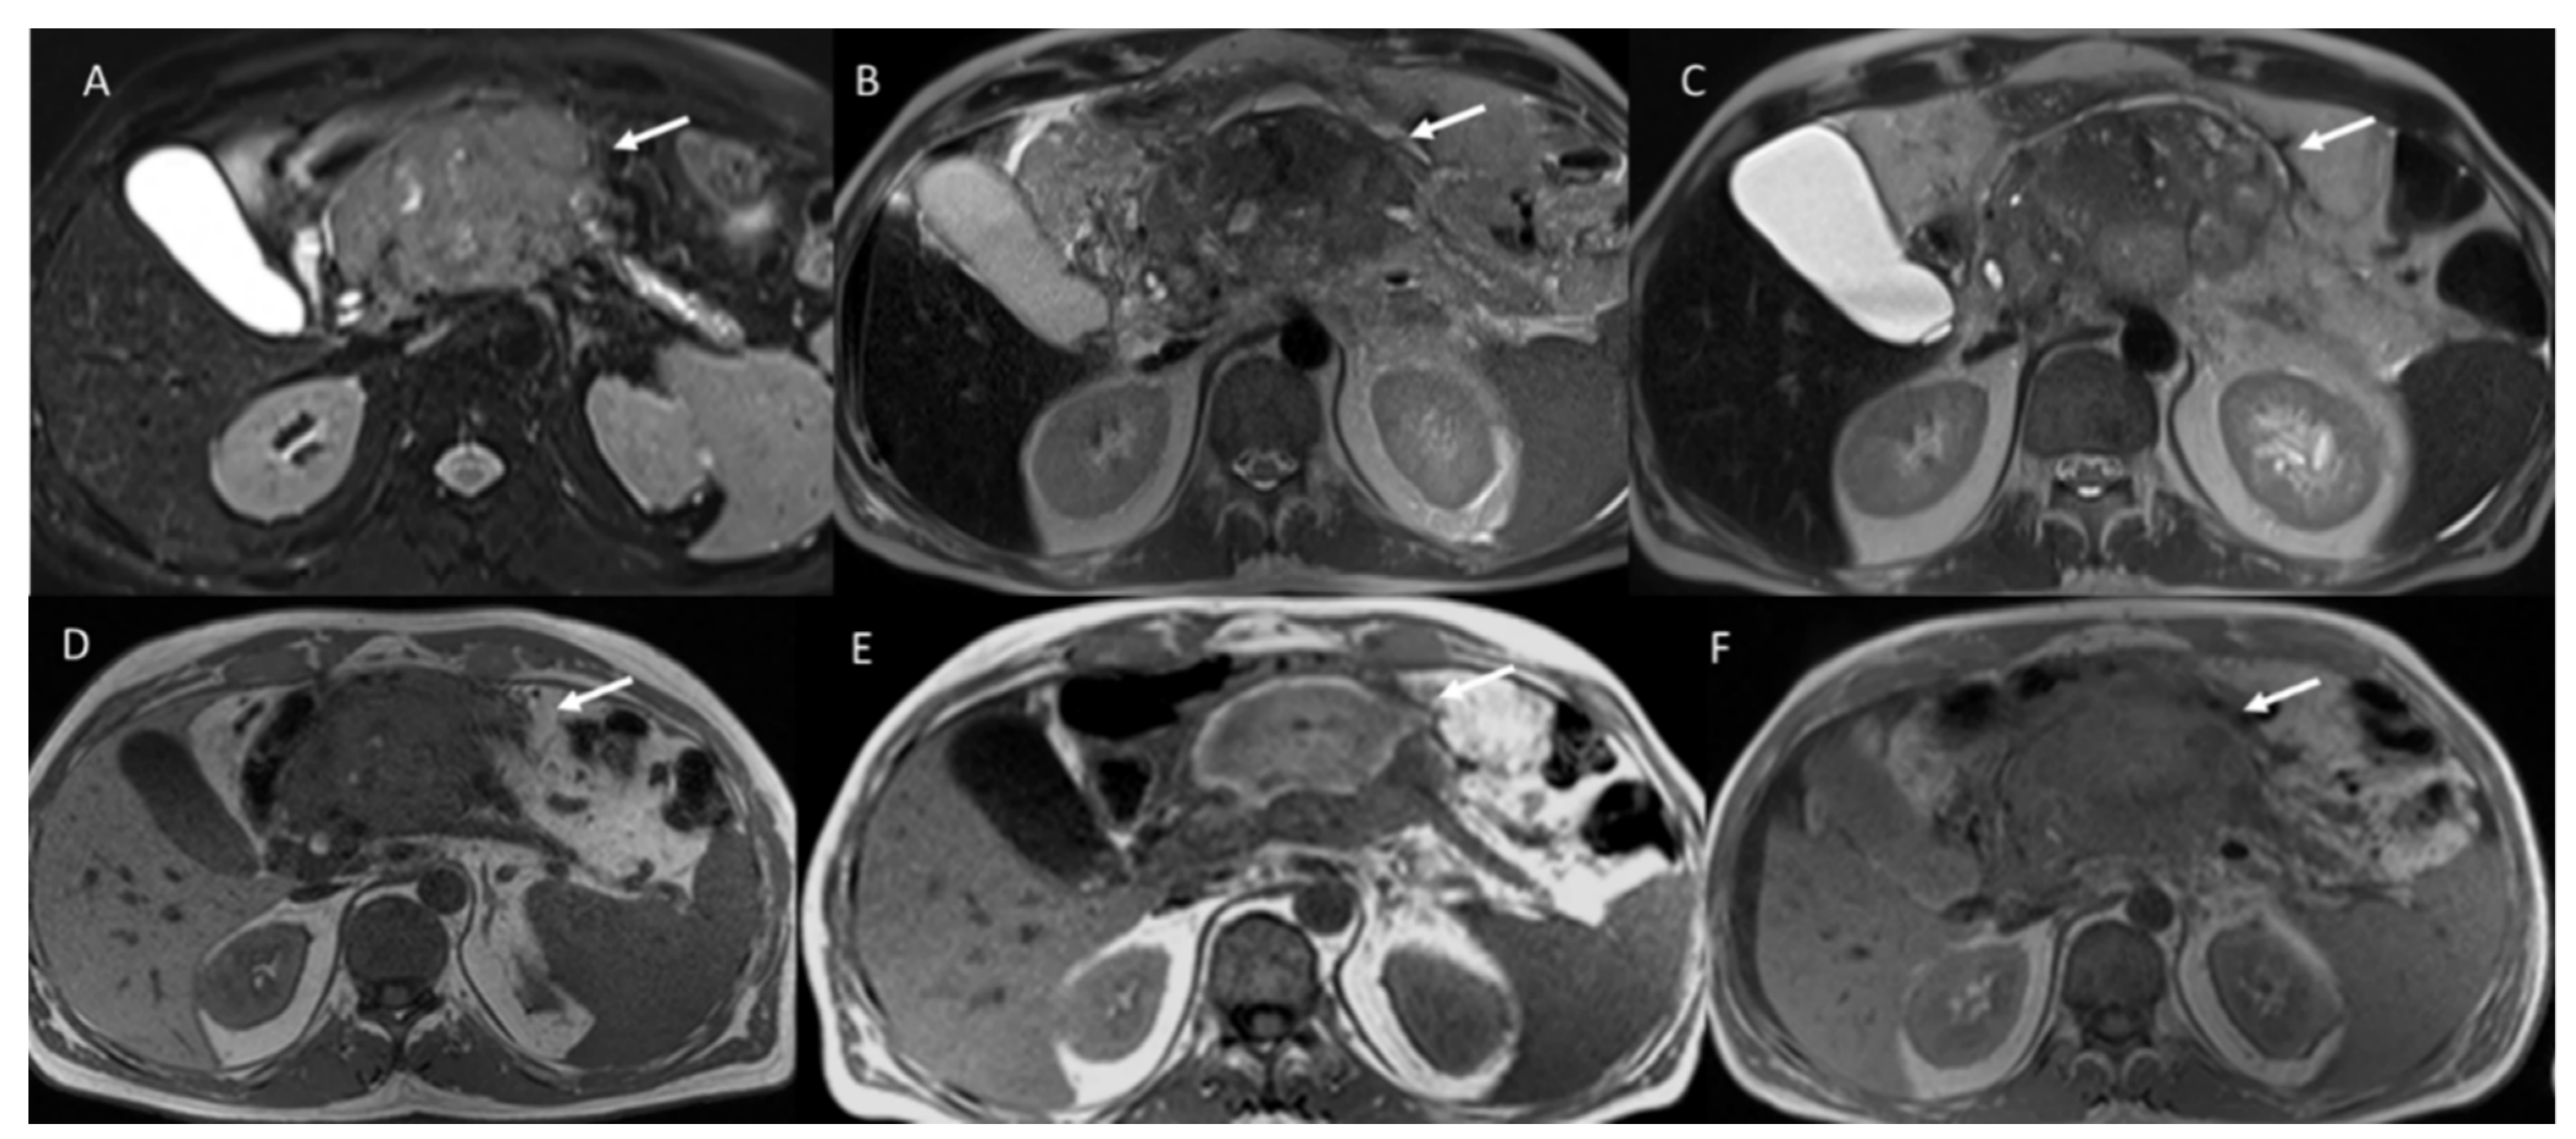

| Magnetic Resonance Imaging | Persistent enhancement of the peritumoral liver parenchyma is observed within the IRE ablation zone. | On T1-weighted images, treated responsive lesions showed a nonhomogeneous signal, with a hyperintense central core and a hypointense peripheral rim. On T2-weighted sequences, the signal from the necrotic ablation zone was heterogeneously hypointense. The residual tumor tissue appeared as a peripheral portion that was hypointense on the T1-weighted images and hyperintense on the T2-weighted images. Three distinct layers on MRI in the irreversible electroporation ablation zone are visible: an inner layer of coagulative necrosis (hyperintense at T1- and T2-weighted imaging and non-enhancing), a middle layer of congestion and hemorrhage (hypointense at T1-weighted imaging, hyperintense at T2-weighted imaging, and progressively enhancing but hypointense at the hepatobiliary phase), and a peripheral layer of inflammation (hyperintense at the arterial phase but isointense at all other sequences). | On ceMRI spherical, oval or oblong area dependent to the number and type of electrodes used are visible. Treated lesion is heterogeneously or peripherally hyperintense on T1-weighted images and heterogeneous or hypointense on T2-weighted because of coagulative necrosis, hemorrhagic products and dehydration. The ablation zone is well demarcated, and no enhancement suggests a lack of viable tumor | [68,85,87,88,89,90,91] | |

| Responsive area 5 months after the treatment is observed as fibrotic residuum without the hypointense peripheral rim. | On ceMRI treated responsive area are visible as devascularized areas with or without an ablative margin or linear enhancement within the lesion. The ablation zones containing residual viable tumor showed contrast enhancement during the arterial phase and portal phase washout. The residual tumor tissue appeared as hypointense, although to a lesser degree than the necrotic portion, in the hepatobiliary phase | ||||

| On ceMRI, no intravascular or perivascular enhancement was observed in responsive area. | On DWI, treated lesions showed restricted diffusion. | ||||